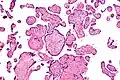

Micrograph of villitis of unknown etiology. H&E stain.

Histopathology

Histomorphologically, VUE is characterized by a lymphocytic infiltrate of the chorionic villi without a demonstrable cause. Plasma cells should be absent; the presence of plasma cells suggests an infective etiology, e.g. CMV infection.